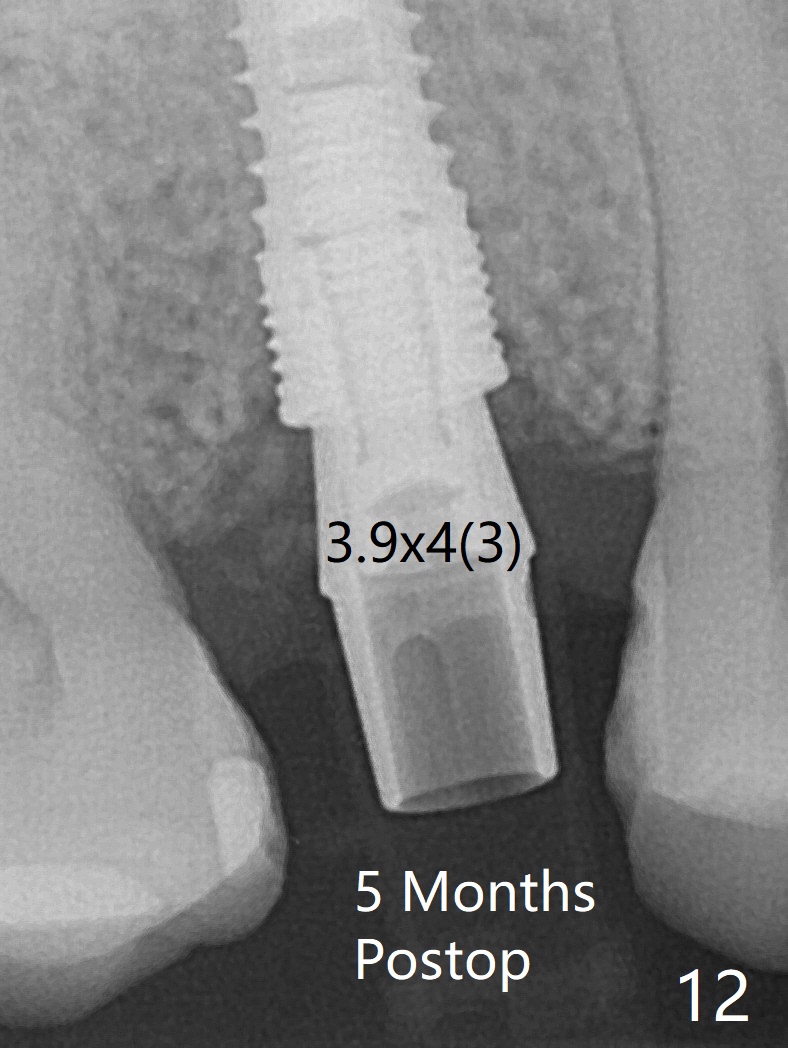

40岁女右上5近中龈下龋齿(图一),要求拔除植牙,上颌窦底板已经破坏穿孔,但是窦膜完整(图二)。清创后,放置PRF膜和粘性骨粉,用挖匙和上颌窦充填器尽量往上面推。然后放置导板,使用2.2x7.3 和3.0x7.3毫米钻头完成钻洞,可能无意中把骨粉推入上颌窦,之后利用报废植体(图三,四)完成提升,同时修补根尖缺损(利用之前放置的骨粉,图四:*,与图五(术前)对比)。当报废植体取出时,植牙窝已经形成,再放入少量骨粉,植入同样大小(之前扭力高)正式植体(不同品牌,图六,七),这时扭力低,放置愈合帽和骨粉(图七,八),以及6-9个月吸收膜,使用牙周胶水固定(图九),最后牙周敷料。术中术后几个小时没有上颌窦膜破裂迹象。术后一周牙周敷料松动,造成不适,去除时,膜好像粘附于敷料一起去除,骨粉暴露(图十),使用树脂敷料固定。后者术后一个月去除,因为局部有臭味。术后4个月切开放置愈合基台(图十一),术后五个月放置修复基台(图十二),使用塑料袖取模。术后5.5月同时放置牙冠和基台,十分顺手,口内粘固,之后同时取出,除去多余粘固剂,然后拧紧30Ncm(厂家推荐35 Ncm),一切非常顺利,觉得拍摄X光片是多余的。美中不足的是开孔(access hole)偏腭侧(图十二;由于自由手植入植体,与设计对比)。